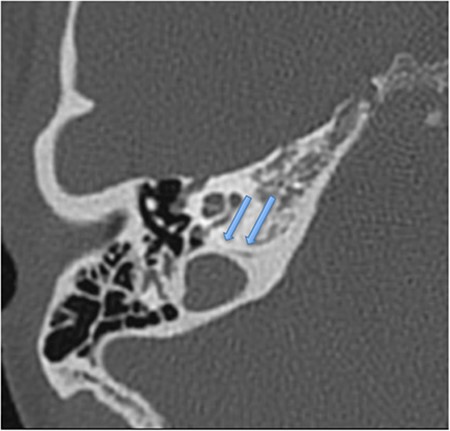

A 26-year-old woman, primigravida and primipara, was admitted to the institution with spontaneous labour at full term. Emergency caesarean section was deemed necessary due to a prolonged latent phase of labour and foetal distress concerns as seen on cardiotocography. The patient was placed in an appropriate position for skin preparation with chlorhexidine, and then local infiltration was performed using 3 ml of 2% lidocaine. An 18-guage needle was used for the epidural catheter placement, and loss of resistance technique was used to identify the epidural space. The needle was inserted 5.5 cm cephalad into the epidural space at L3–4 by the midline approach. Then 12 ml of 0.2% ropivacaine and 16 micrograms of fentanyl was injected, followed by a ropivacaine and fentanyl infusion. Surgery was completed within 45 minutes, and no intraoperative complications transpired. Haemodynamic parameters remained normal throughout the perioperative period. The epidural catheter was removed within 12 hours postoperatively, with no complications. Day 1 postoperatively, the patient reported a sensation of light-headedness and dizziness but no headache. Day 2 postoperatively, she was discharged at home. No ototoxic medications were administered during admission or dispensed on discharge. On the same day, the patient noticed a constant right ear hearing loss, ongoing unbalance, a sensation of aural fullness and high-pitched non-pulsatile tinnitus. She attended her local primary care physician the same day and was treated with intranasal corticosteroids for possible eustachian tube dysfunction. Persistence of symptoms for 2 weeks prompted an audiological assessment which diagnosed a SNHL (Fig. 1). Urgent ENT specialist advice was sought over the phone, and the patient was commenced on systemic corticosteroids for 7 days (1 mg/kg of prednisone). The patient has no previous ear symptoms, no prior ear surgery, trauma or recent upper respiratory tract infection. A posterior fossa magnetic resonance imaging scan was performed but found no pathology. High-resolution temporal bone computed tomography (CT) scan demonstrated an enlarged right cochlear aqueduct (Fig. 2). Repeat audiological assessment in 2 weeks showed no pure tone audiometry change, but significant improvement in speech discrimination was present (53–90%). The patient was then seen in a specialist ENT clinic. Physical examination including microscopic otoscopy was unremarkable. Unilateral hearing loss management options were discussed with the patient, with conventional hearing amplification recommended. Repeat audiogram at 4 and 10 months’ time showed no further improvement but stabilised hearing. The patient has declined the use of amplification, and a recommendation to avoid further spinal-epidural anaesthesia was given.

Hearing loss following non-cardiac surgery involving combined spinal-epidural anaesthesia has been reported before; however the incidence is estimated to be very low [4]. The majority of these cases involve temporary hearing loss, which typically returns to normal in 5–15 days. Hearing loss occurring primarily in lower frequency ranges (125–1000 Hz) [5]. Permanent hearing loss post spinal anaesthesia has been documented but is often combined with vertigo and tinnitus and is extremely rare [3]. The mechanism is theorised to result from disruption of the endolymph/perilymph balance caused by the decrease in cerebrospinal fluid (CSF) pressure due to CSF leakage from the epidural site. Decrease in perilymphatic pressure is transmitted via the cochlear aqueduct, fundus of the internal auditory canal, or the modiolus of the cochlea. This displaces hair cells in the basement membrane, resulting in low frequency hearing loss [6]. Our case describes a patient who underwent a combined spinal-epidural anaesthesia for an emergency caesarean section and subsequently suffered hearing loss which did not self-resolve in the usual time expected, was not associated with headache, and did not significantly improve post systemic corticosteroid administration. To the authors’ knowledge, there is only one similar report of SNHL following spinal-epidural anaesthesia without headache [7].